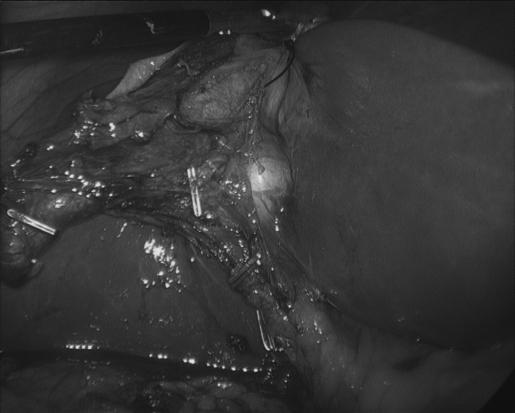

Laparoscopic excision of a ciliated hepatic foregut cyst.

Ciliated hepatic foregut cysts are uncommon solitary cysts of the liver that originate from the embryologic foregut. Clinically and radiographically, these lesions can be difficult to distinguish from neoplasms. Recent reports have demonstrated that ciliated hepatic foregut cysts may undergo dysplastic progression, supporting the argument to excise these cysts when discovered. Fewer than 100 cases have been described in the literature since the first description of a ciliated hepatic foregut cyst in 1857. We present a patient who recently underwent laparoscopic excision of a ciliated hepatic foregut cyst, review the literature, and propose the rationale for attempting removal of these cysts via a laparoscopic approach.